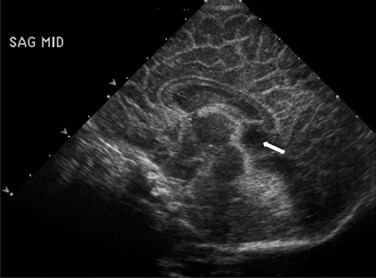

Neonatology Cavum Veli Interpositi Image